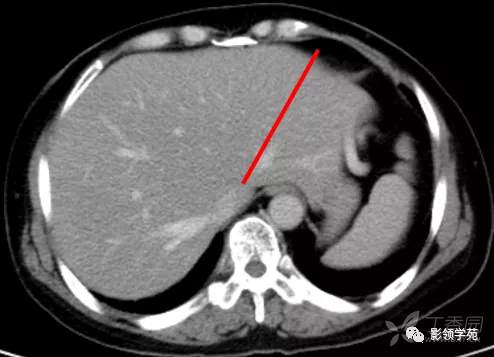

肝脏八段分法的影像学解剖示意图

胆囊窝层面CT横断面解剖

CT:首先找出肝脏的三大静脉:肝中静脉,肝左静脉,肝右静脉,找出门静脉及其分叉部位。门静脉分叉部位可以区分上段和下段,即肝S8/S5,S7/S6,门静脉分叉以上为S8、S7;肝右静脉和肝中静脉之间是右前叶,肝右静脉以后是右后叶

一般规律,从CT上看,最先看到的是S8然后是S2、3,肝左外叶以肝裂为界,左内叶为肝裂和肝中静脉之间的区域,胆囊往下的层次是S5,最后的层面一般是S6,下腔静脉和门静脉夹着的是尾状叶,即S1。